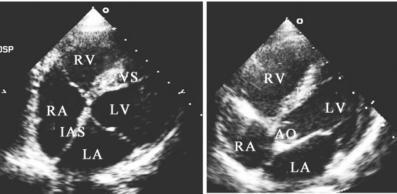

1.14.2.2二、常用切面图及用途

-